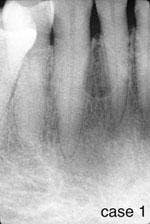

CASE 1

Lateral periodontal cyst (LPC)

1. Where is the LPC likely to occur?

a. mandibular canine area

b. mandibular incisor area

c. mandibular premolar area

d. all of the above

2. What is the radiographic appearance of the LPC?

a. round/ovoid radiolucency, well-defined borders

b. round/ovoid radiolucency, ill-defined borders

c. round/ovoid radiopacity, well-defined borders

d. round/ovoid radiopacity, ill-defined borders

3. What is the preferred treatment for the LPC?

a. no treatment is necessary

b. surgical removal

c. laser surgery

d. none of the above